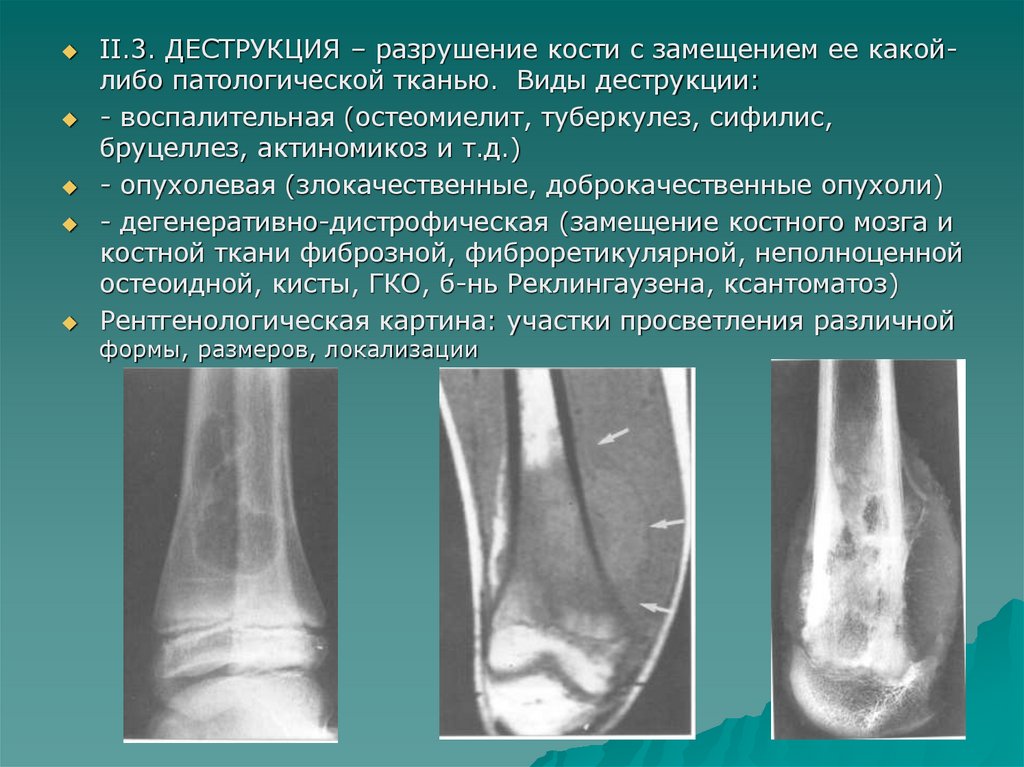

II.3. ДЕСТРУКЦИЯ – разрушение кости с замещением ее какойлибо патологической тканью. Виды деструкции:

- воспалительная (остеомиелит, туберкулез, сифилис,

бруцеллез, актиномикоз и т.д.)

- опухолевая (злокачественные, доброкачественные опухоли)

- дегенеративно-дистрофическая (замещение костного мозга и

костной ткани фиброзной, фиброретикулярной, неполноценной

остеоидной, кисты, ГКО, б-нь Реклингаузена, ксантоматоз)

Рентгенологическая картина: участки просветления различной

формы, размеров, локализации